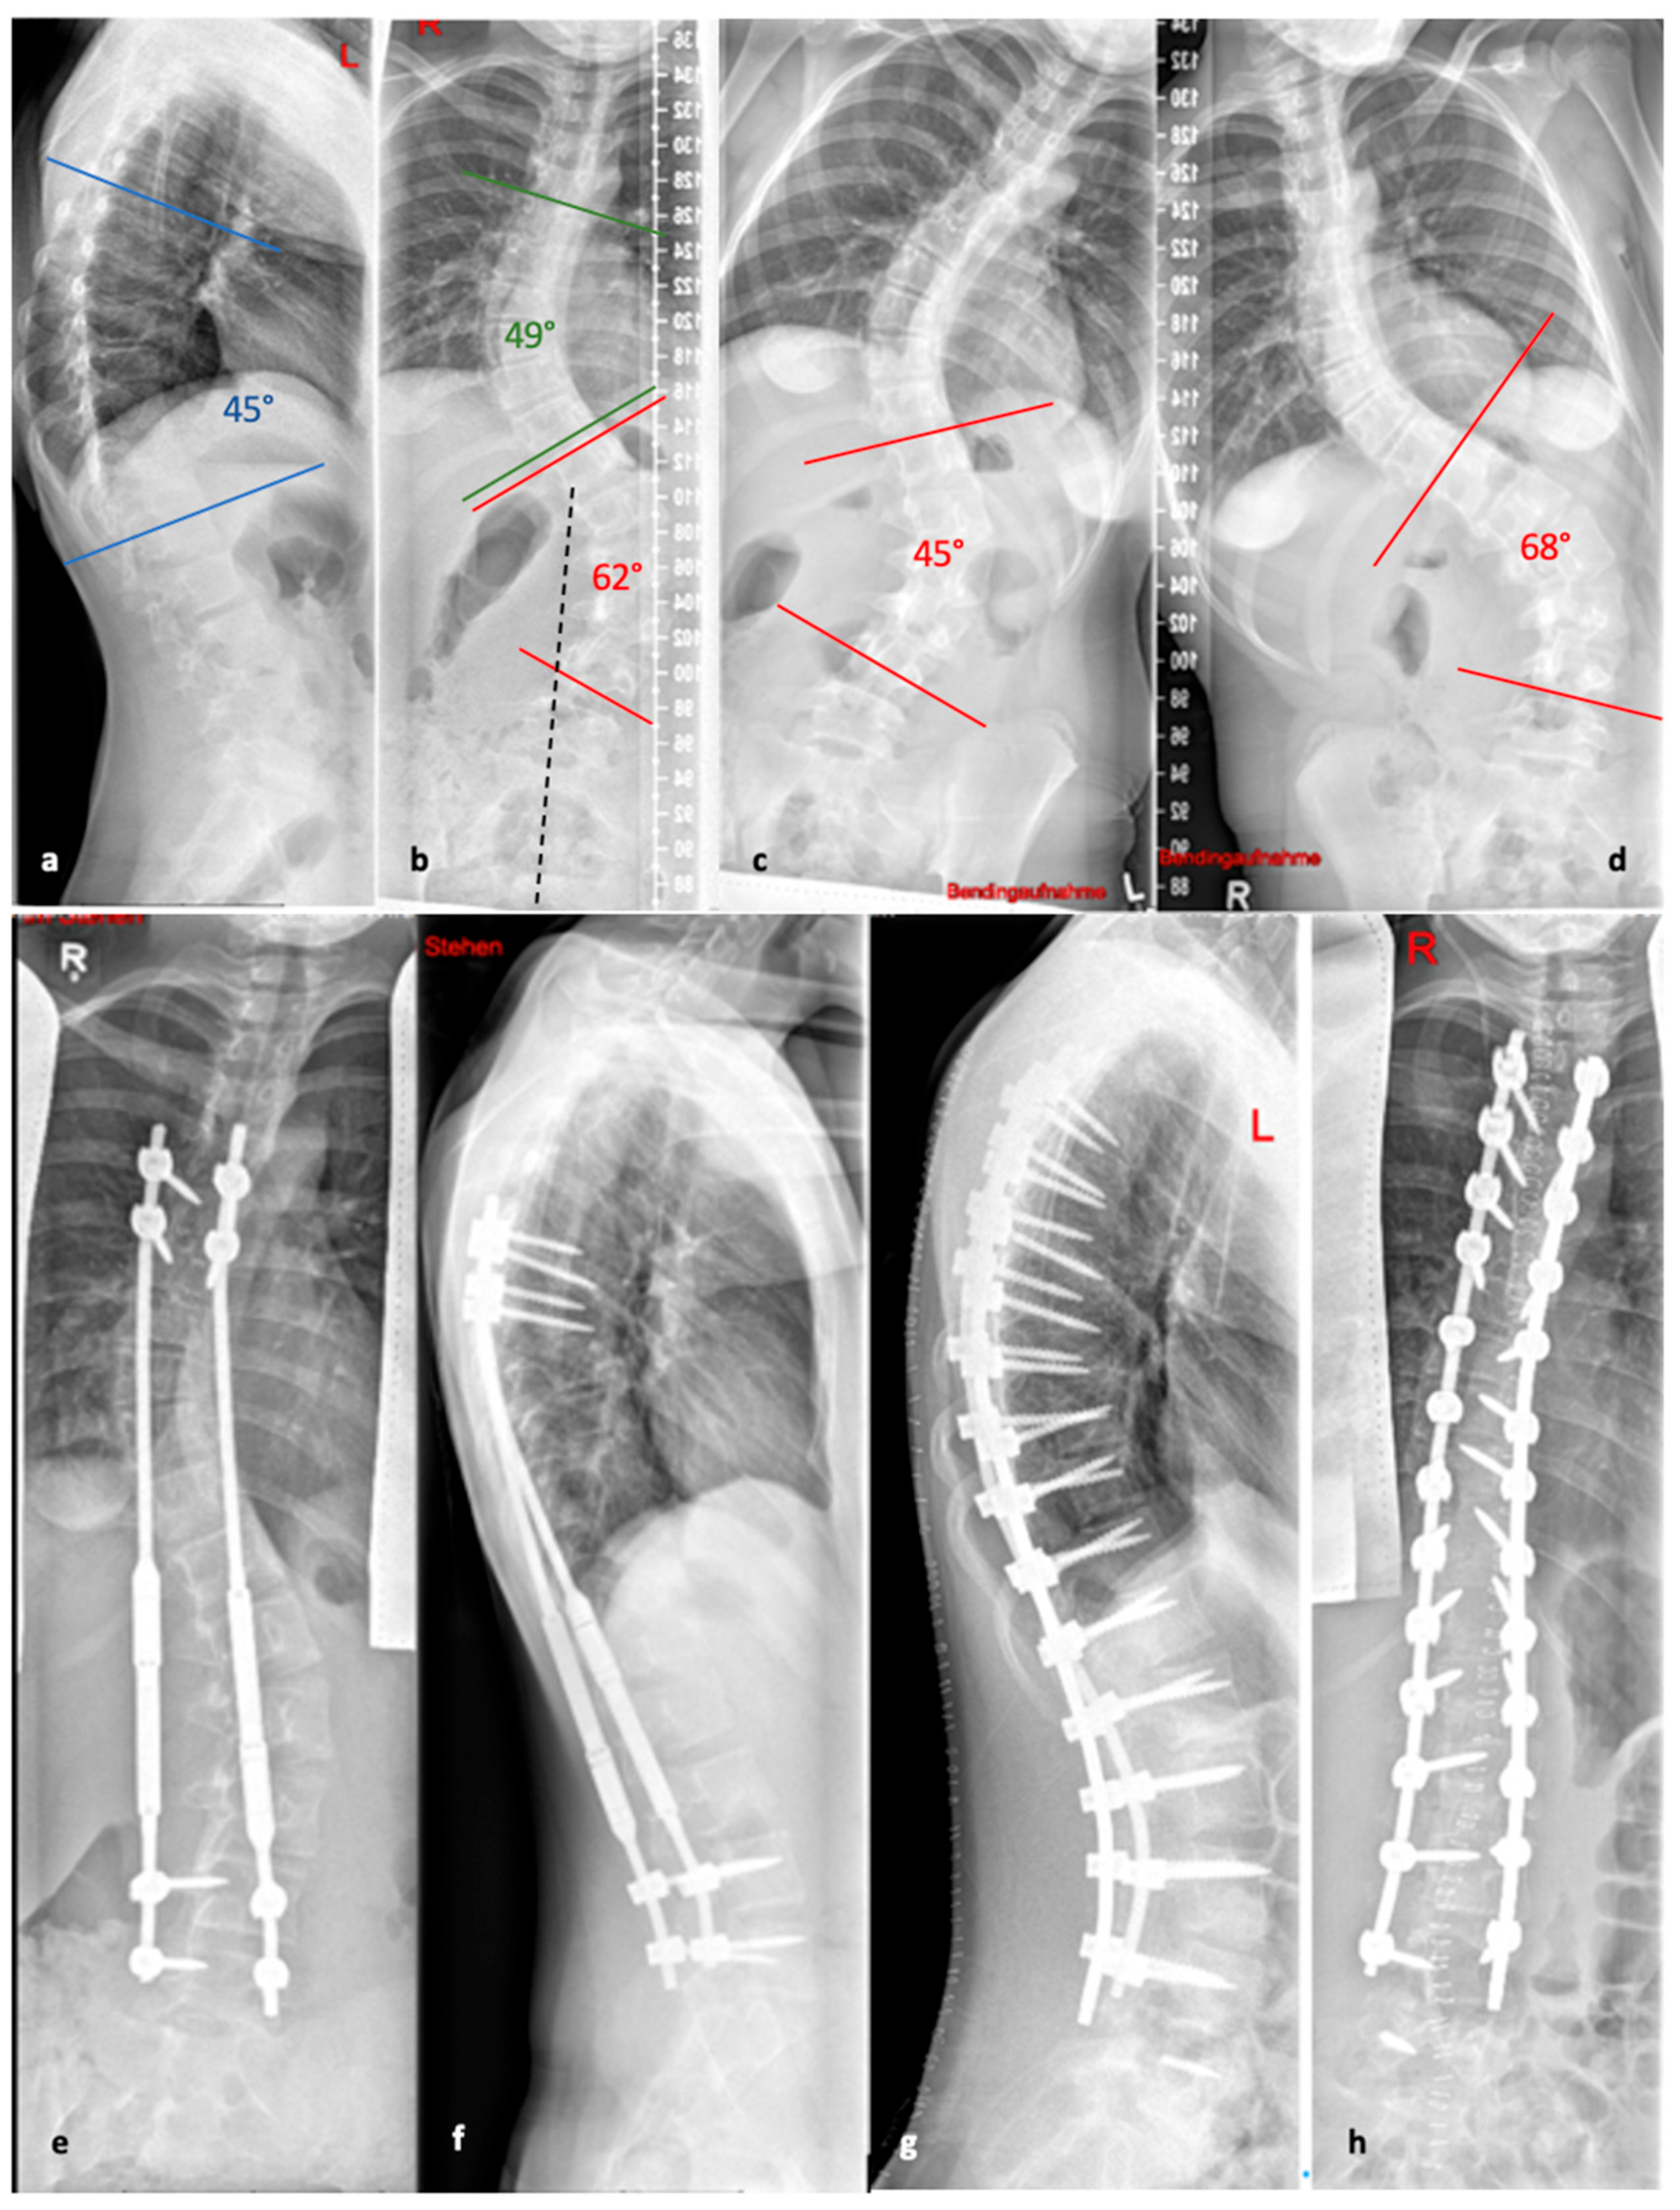

To avoid the regular surgical lengthening procedure, MCGRs were developed and approved for the treatment of EOS in Europe in 2009. MCGRs are telescopically extendable distraction rods. They can be distracted non-invasively, on an outpatient basis, by externally magnetically controlled lengthening using electromagnets. Figure 5 illustrates the progression of treatment for a patient with AIS, starting from initial diagnosis, through the bending radiographs, to the postoperative phase with implanted MCGR, and finally, the maintenance phase involving spondylodesis.

Figure 5. (a,b). Initial radiographs of a patient with adolescent idiopathic scoliosis. (c,d). Bending radiographs. (e,f). Postoperative image displaying implanted magnetically controlled growing rods as a dual rod system. (g,h). The patient was treated with a spondylodesis upon the completion of growth to maintain correction success (Reprinted with permission [10]).